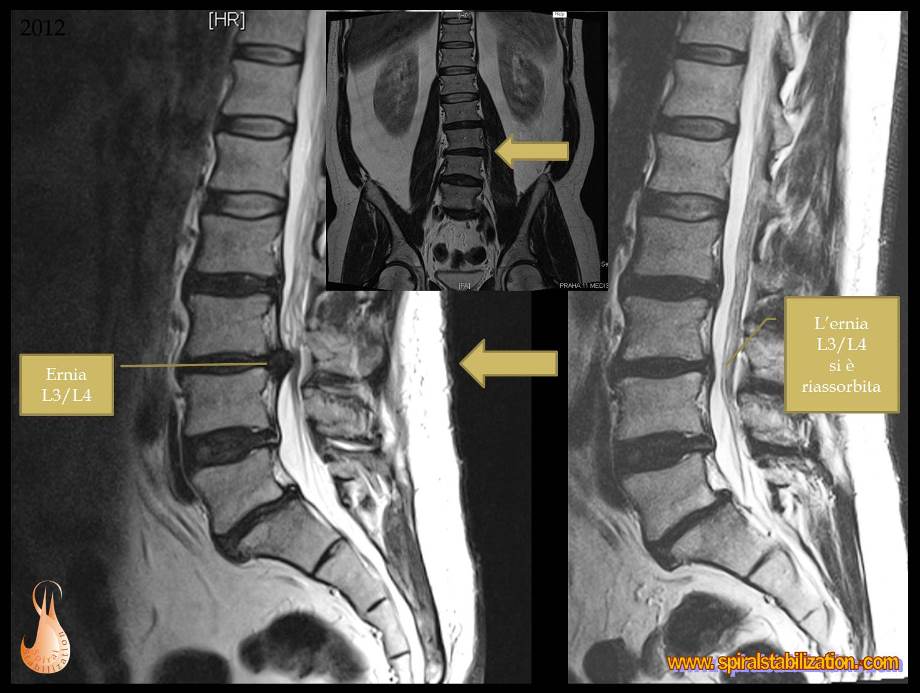

1 - Ernia L3/L4

B - 1 - 1 -1

Ernia del disco L3/L4